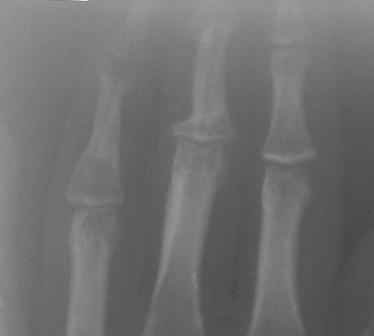

Re: Непонятный процесс в основной фаланге пальца

Уважаемый Юрий, действительно, онкологи делали пункционную биопсию.

Конечно, мы во время операции будем брать материал на гистологию, а также удаление очага и замещение аутотрансплантатом тоже в плане рассматривается, как на примере, которая была представлена на форуме. правда снимки не очень качественные, прощу извинения!

Коллеги, почти уверен, что эти два случая поражения фаланг имеют различный генез. Простое выявление хрящевой ткани в биопсийном материале, увы, не дает еще диагноза.. Хотя местное лечение (если оно необходимо) может быть сходным. Единственное, не стал бы увлекаться широкими резекциями и массивными костными пластиками в детей.